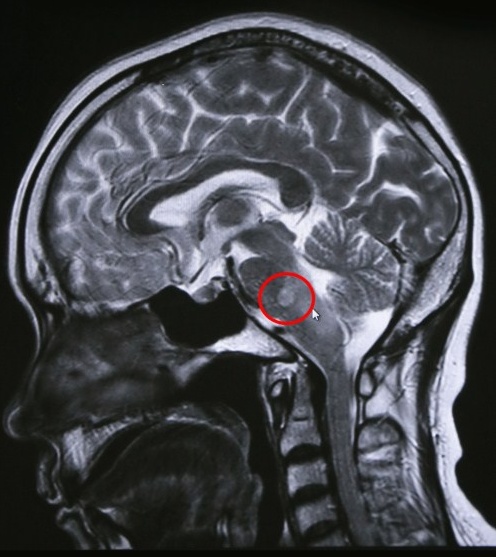

说起孙主任的“科技眼”,给他看过片子的病人们都记忆深刻,不少病人说:“孙医生的眼睛,挽救了我的一条性命。”这双眼睛,使数不清的患者避免了不必要的手术,也使数不清的患者能在疾病的萌芽阶段及早治疗诊断,得到及时治疗,避免了大手术。南通的一位患者在多家三甲大医院检查,都说他得了脑部肿瘤要做手术,后来,在蓝十字脑科医院做了MR,经认真仔细的读片后,孙海辉主任认为这是炎性病变,不是肿瘤,只要药物保守治疗即可,病人免了开刀之痛苦,对孙主任千恩万谢。

脑干炎性病变非肿瘤